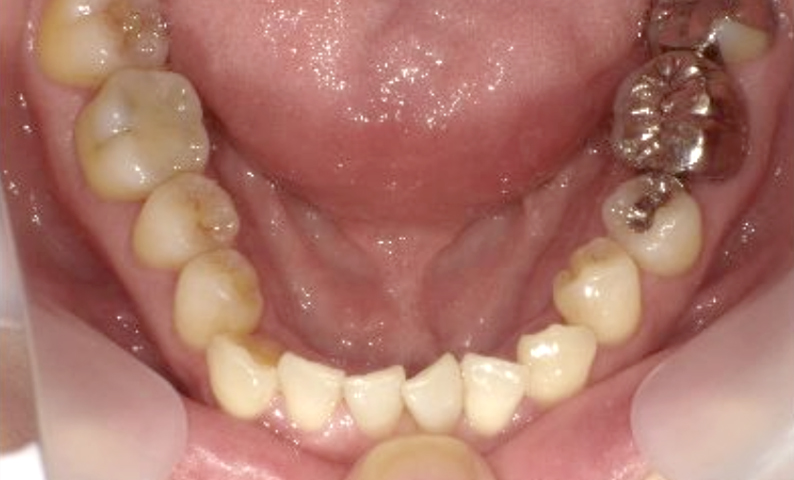

症例_003 下顎だけの部分矯正

治療期間:10ヶ月金額:24万円+税女性前歯のガタガタ下の前歯だけ上顎は補綴治療中

| Before | After |